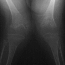

Valgus deformity of the knees, associated to flexion contracture,

is another common finding.

- Long bones: they are broad and short. Metaphyses are flared and expanded.

A chevron-like shape is often present in femoral and tibial metaphyses.

Epiphyseal centers appear late and are severely irregular and flat. Ulna

and fibula are usually short.